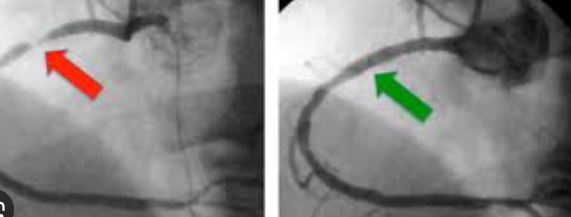

Patients often ask how CT coronary angiography compares to conventional coronary angiography. Understanding the difference helps in making an informed choice.

CT coronary angiography — non-invasive, no catheter insertion, completed in a short time, same-day discharge

Conventional coronary angiography — invasive, catheter guided through blood vessels, detailed real-time assessment

CT angiography as a gatekeeper — helps avoid unnecessary invasive angiography in suitable patients

<strong>Which test is best for checking heart blockage?</strong> The choice depends on symptoms, risk factors, and cardiologist evaluation. CT coronary angiography is often preferred for initial non-invasive assessment, with conventional angiography reserved for cases requiring more detailed or interventional evaluation.